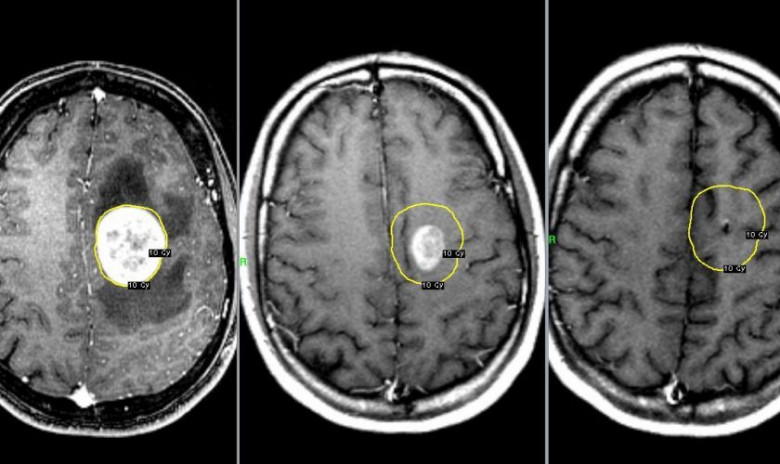

Գլխուղեղի ուռուցքի 10 առաջին նշանները, որոնց մասին պետք է յուրաքանչյուրն իմանա

Ներկայացնում ենք գլխուղեղի ուռուցքի 10 առաջին նշանները, որոնց մասին պետք է յուրաքանչյուրն իմանա: